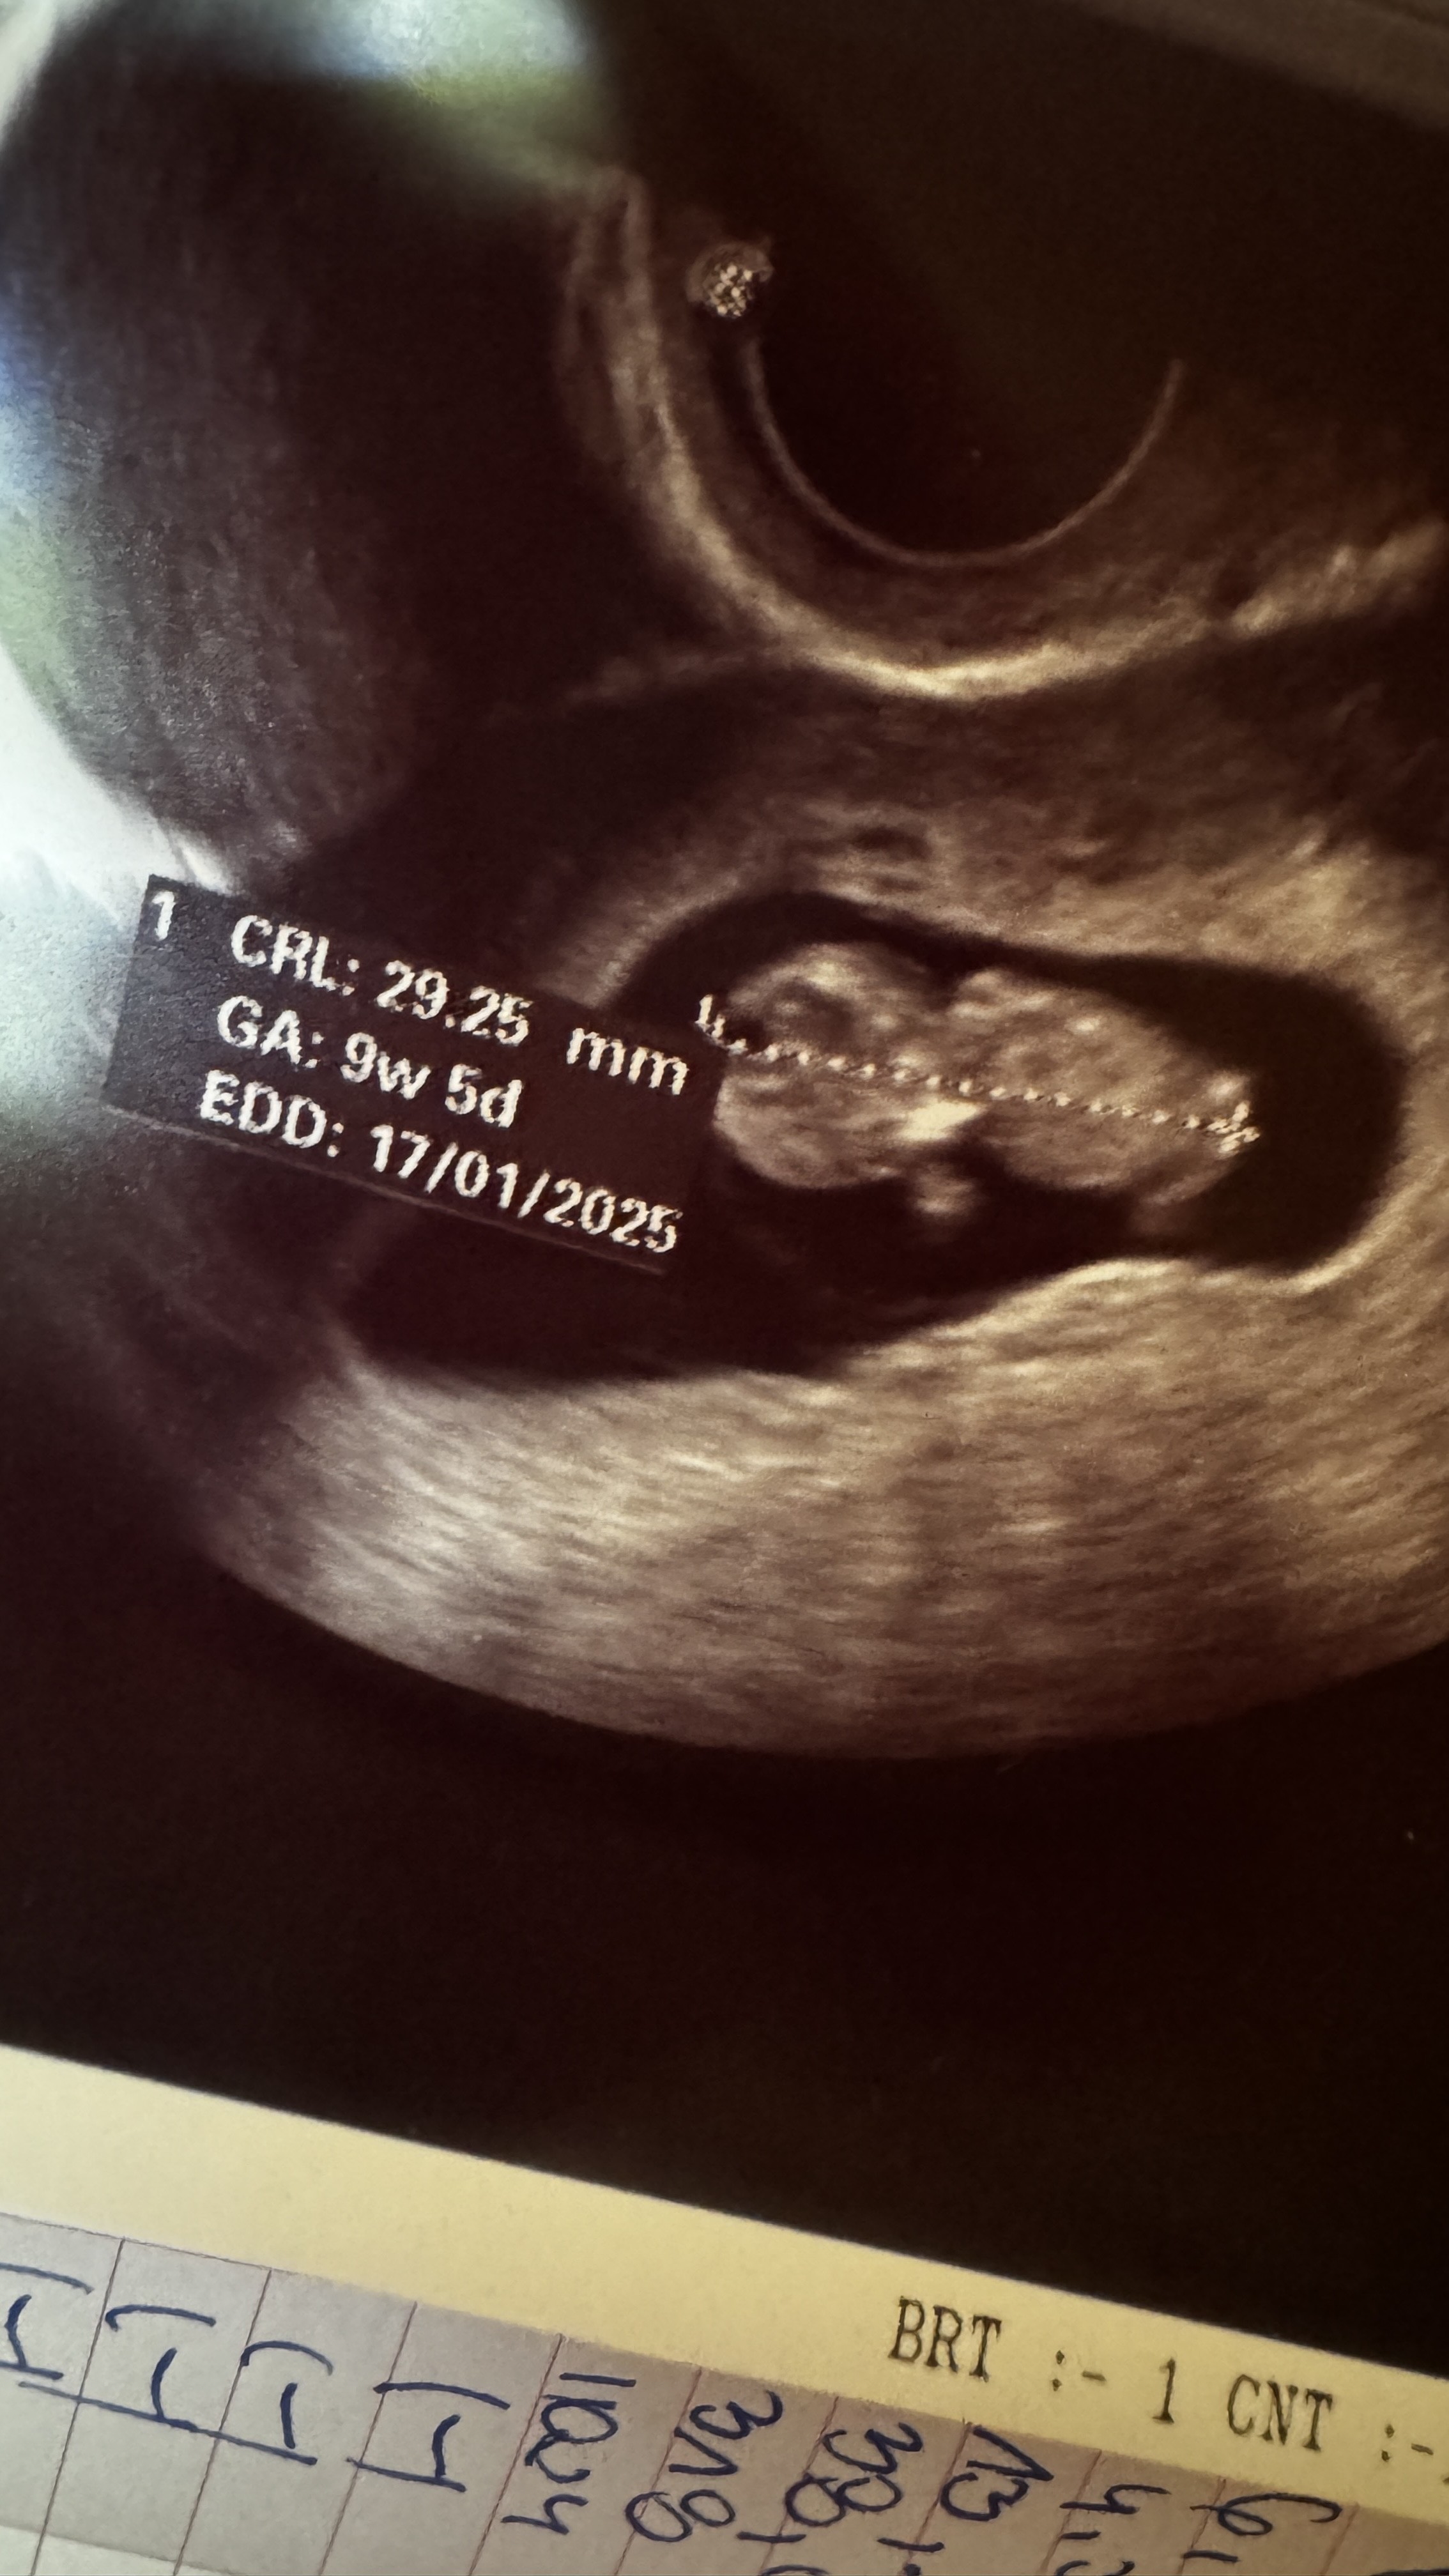

Ja jeszcze do siebie nie doszłam . Mogłam wręcz uwierzyć ,że to serduszko. Kilka razy pytałam czy na pewno to serce bije. Schowało się za łożyskiem i się śmiało z mamy

a co tam. Zrobię mamie psikusa . Mąż stwierdził od razu,że to po nim ma. Tak.tak. on też potrafi napędzic mi niezłego strachu swoimi żartami . Lekarz żeby udowodnić mi ,że żyje przestał ruszać głowicą USG a ono sobie pięknie pływało . Patrząc na zdjęcie faktycznie jest odwrócone tak,że może i ciężko było znaleźć serduszko . Bardziej widać główkę niż całą resztę . Ale jestem szczęśliwa jak chyba nigdy.